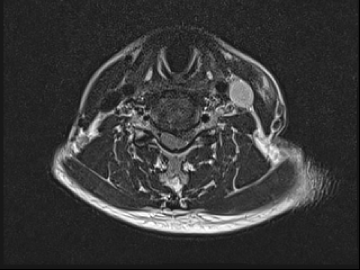

고주파수핵성형술

2017.08.07

ㆍ환자 동의를 받은 자료이며, 이미지 사진은 실물과 다를 수 있습니다.

ㆍ모든 자료는 새움병원 자료입니다.